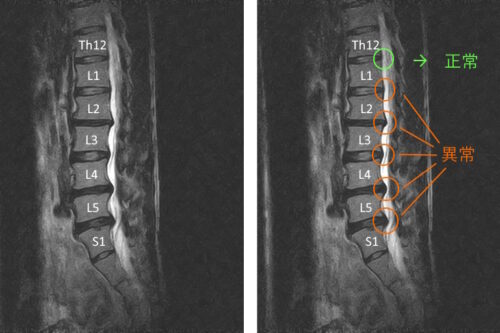

【症例】重度の腰椎椎間板ヘルニアと診断された40代男性、腰痛と左おしりからふくらはぎまでの…